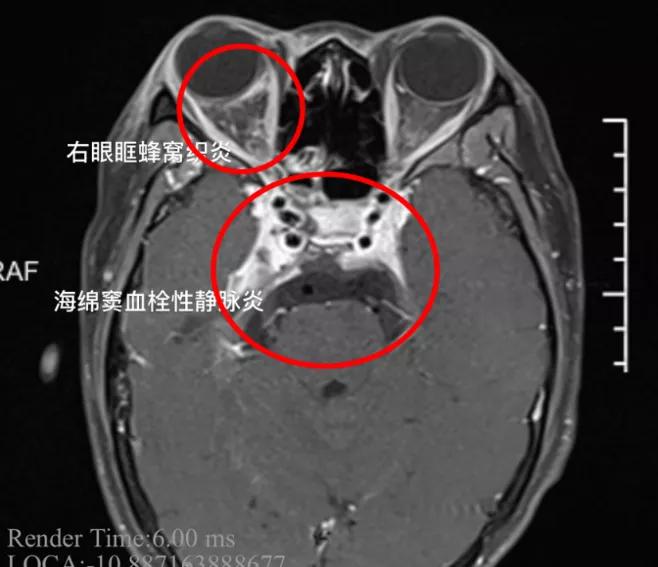

经医生诊断,小杨患上了“海绵窦血栓性静脉炎”,这是一种严重的颅内感染。

接诊医生表示,小杨被送来时,多组颅神经受累,同时脑膜刺激征阳性,海绵窦的炎症已经扩散,出现了脑膜炎。

如果不及时治疗,随时有生命危险。